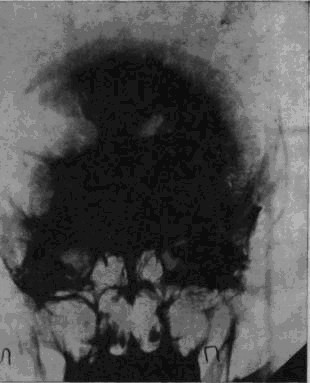

«Младший лейтенант Засецкий, 23 лет, получил 2 марта 1943 года пулевое проникающее ранение черепа левой теменно-затылочной области. Ранение сопровождалось длительной потерей сознания и, несмотря на своевременную обработку раны в условиях полевого госпиталя, осложнилось воспалительным процессом, вызвавшим слипчивый процесс в оболочках мозга и выраженные изменения в окружающих тканях мозгового вещества».

Рис. 1а. Рентгеновский снимок черепа больного Засецкого после введения воздуха в желудочки мозга (пнеймоэнцефалограмма). На нем можно видеть резко расширенный левый боковой желудочек и скопление воздуха в подоболочечных пространствах мозга теменно-затылочной области левого полушария

Осколок внедрился в вещество задних, теменно-затылочных отделов мозга и разрушил мозговую ткань этой области.

Ранение осложнилось воспалительным процессом; он не распространенный, местный, ограничен лишь областями мозга, примыкающими к непосредственному месту ранения, но теменно-затылочные отделы левого полушария, отделы, так тесно связанные с анализом пространственного мира, необратимо повреждены, и уже начинается процесс образования рубцов, который неизбежно повлечет за собою частичную атрофию расположенных вблизи ранения участков мозгового вещества.

И через десять лет после ранения – еще одна выписка из истории болезни, на этот раз сделанная на основе рентгенограммы.

В спинномозговой канал введен воздух. Он поднялся вверх, заполнил контуры желудочков мозга и те пустоты, которые образовались в результате сморщивания вещества отделов мозга, непосредственно примыкающих к месту ранения. «Процесс рубцевания вызвал атрофические изменения в левом боковом желудочке. Стенки его подтянуты к поверхности мозга, подоболочечные пространства резко расширены. Значительный местный атрофический процесс».

Ранение вызвало местную атрофию мозгового вещества левой теменно-затылочной области.